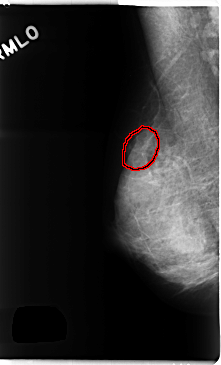

C_0257_1.RIGHT_MLO

FILE: C_0257_1.RIGHT_MLO.OVERLAY

TOTAL_ABNORMALITIES 1

ABNORMALITY 1

LESION_TYPE MASS SHAPE OVAL MARGINS OBSCURED

ASSESSMENT 4

SUBTLETY 3

PATHOLOGY BENIGN

TOTAL_OUTLINES 1

BOUNDARY

RIGHT_MLO LINES 4744 PIXELS_PER_LINE 2864 BITS_PER_PIXEL 12 RESOLUTION 50 OVERLAY